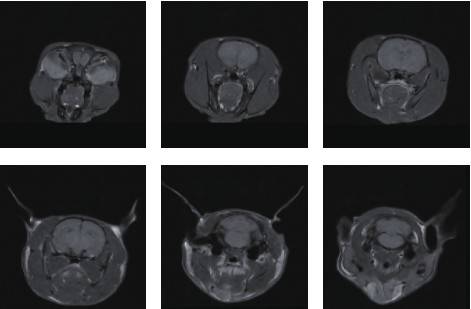

Magnetic resonance imaging (MRI) is widely used in preclinical research and drug development as a powerful, non-invasive method for assessing mouse disease models and treatment efficacy. Small-animal in vivo MRI enables longitudinal evaluation of tissue changes and phenotypic expression in experimental models. Niumag’s compact MRI systems fit into most standard labs—without the high cost and complexity of conventional MRI—providing a high-performance platform for in vivo imaging of small animals. This article introduces the research applications of Niumag’s compact, high-performance small-animal MRI platform in preclinical toxicology and pathology.

Small-animal MRI is a robust, non-invasive in vivo assessment tool for preclinical studies, drug discovery, and disease models. In preclinical workflows, in vivo MRI supports longitudinal studies to monitor disease onset, regression, and therapeutic response—non-invasively and without sacrificing animals at time points. The same animal can be imaged across multiple disease stages, reducing inter-subject variability.

Niumag’s series of compact, high-performance small-animal MRI platforms feature a new magnet design and application software, purpose-built for in vivo studies. These systems remove the cost and complexity barriers of traditional MRI and are easy to learn and operate. Tailored for pathologists without an MRI background, they deliver high-quality in vivo images of laboratory animals—significantly enhancing routine histopathology in preclinical toxicology and rodent disease-model development.

In addition, the platform integrates dedicated hardware/software, pre-programmed protocols, and streamlined sample handling to support high-throughput in vivo imaging for pathologists. Benefits include longitudinal disease monitoring (in vivo MRI) and rapid image acquisition.

Niumag’s compact small-animal MRI is an efficient imaging tool that rapidly delivers in vivo images in rats and mice. Compared with traditional anatomical methods, in vivo MRI requires no invasive procedures, avoiding secondary injury that could confound results. By imaging the same subject repeatedly, researchers obtain more accurate data on disease progression/regression, morphology, and quantitative parameters—greatly enriching study outcomes. Fast scan workflows further boost productivity. As a result, Niumag’s compact MRI has become an essential tool in the life sciences. With ongoing technology upgrades, it will continue to gain adoption and drive new insights and discoveries.